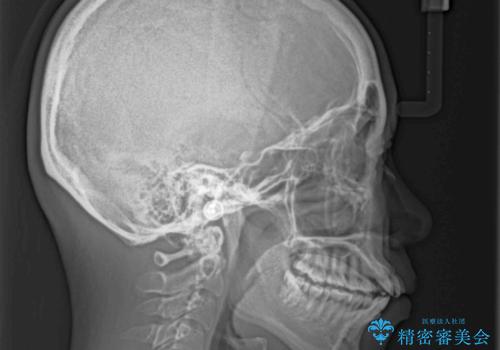

- 前歯のデコボコと口元の突出感を気にして来院された患者様です。

上下左右第一小臼歯4本を抜歯し、ワイヤー装置にて口元を引っ込めるよう矯正治療を行うこととしました。

叢生が強かったため、口元の突出感の改善には限界がありましたが、横側からも口元が引っ込んだ感じが分かるほど改善されました。